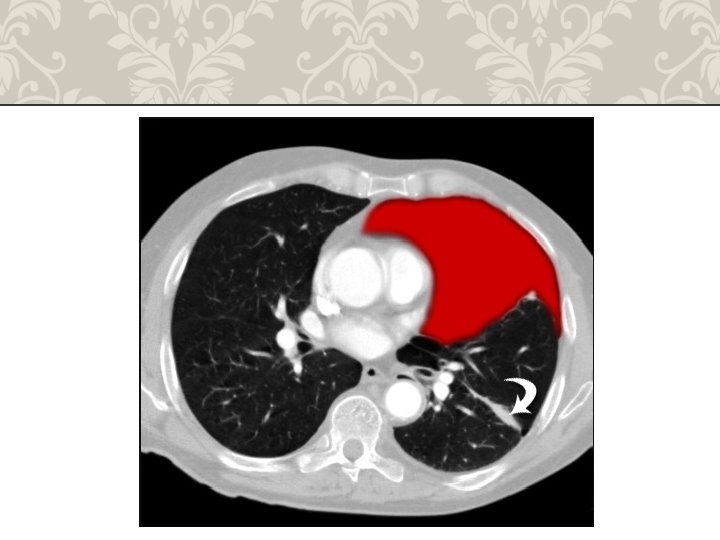

HEMOTHORAX life-threatening injury number one A massive hemothorax is defined as >1500 m. L of blood or, in the pediatric population, one third of the patient's blood volume in the pleural space tube thoracostomy is the only reliable means to quantify the amount of hemothorax After blunt trauma, a hemothorax usually is due to multiple rib fractures occasionally bleeding is from lacerated lung parenchyma a massive hemothorax is an indication for operative intervention Indication of emergency toracotomy

HEMOTHORAX

RIB FRACTURE WITH HEMOTHORAX